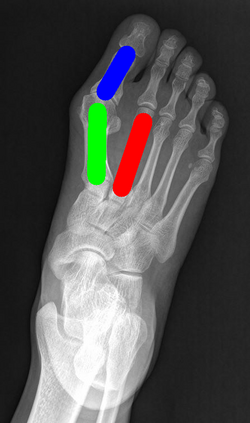

Angular measurements is essential to make a resonable treatment for Hallux valgus (HV), a common forefoot deformity. However, it still depends on manual labeling and measurement, which is time-consuming and sometimes unreliable. Automating this process is a thing of concern. However, it lack of dataset and the keypoints based method which made a great success in pose estimation is not suitable for this field.To solve the problems, we made a dataset and developed an algorithm based on deep learning and linear regression. It shows great fitting ability to the ground truth.